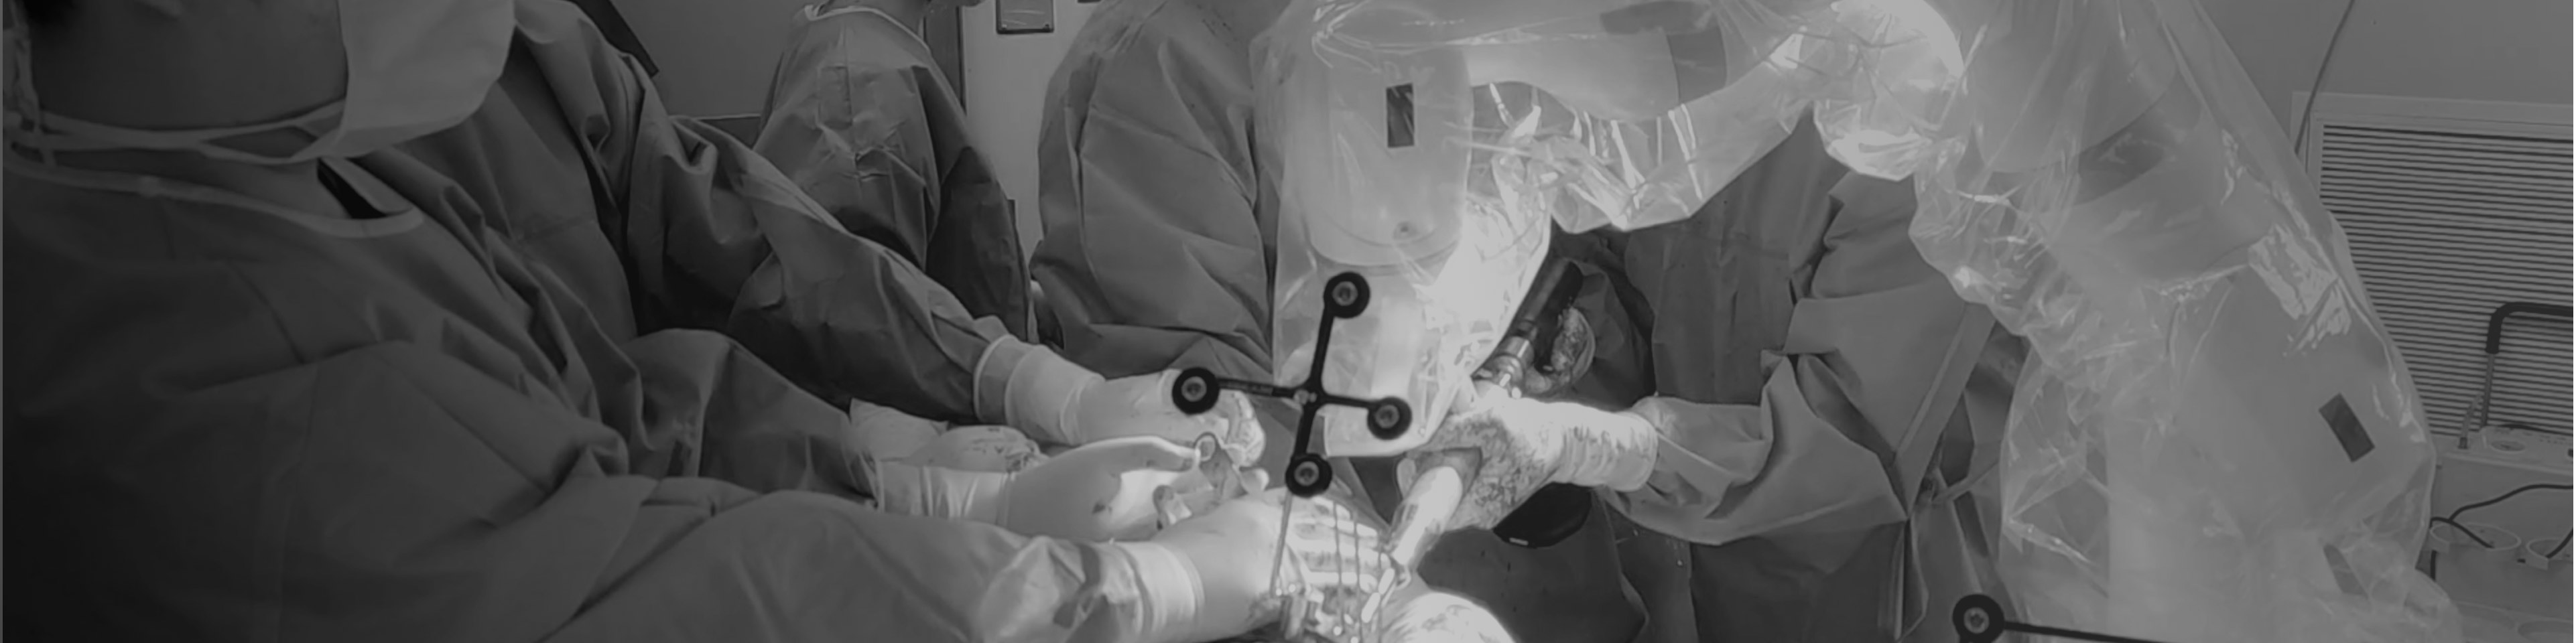

· 穩(wěn)定快速解剖點配準(zhǔn),將術(shù)中生理結(jié)構(gòu)與其術(shù)前影像數(shù)據(jù)建立空間關(guān)聯(lián),保證手術(shù)規(guī)劃的準(zhǔn)確執(zhí)行。配準(zhǔn)時間控制在3-5min。

· 實時顯示磨削進度,指示手術(shù)規(guī)劃的磨削區(qū)域,警示過度磨削。

· 精準(zhǔn)高效執(zhí)行手術(shù)操作,實時安裝角度顯示,誤差控制在1°以內(nèi)。